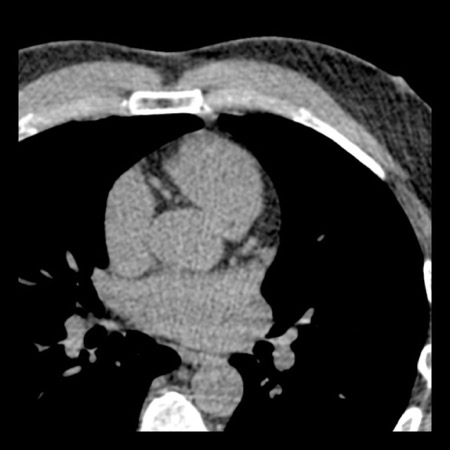

case 3 – Calcium score 0 and severe stenoses.

First, scroll through the CTA images.

How would you describe the findings on the coronary CTA?

The findings are:

- The total calcium

score of 0 indicates the absence of calcified plaque in the coronary

tree. - Severe stenosis

(70-99%) in the mid LAD and D2 branch.